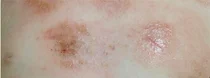

아토피치료제 교차투여 내달엔 급여 될듯

▲아토피 피부염 상태 아토피피부염 치료제의 '교차투여'가 곧 급여화될 것으로 보인다. 4일 건강보험심사평가원과 약업계에 따르면 심평원은 이미 사전약가인하 제도를 통해 교차투여 가능을 검토했고, 제약사들은...